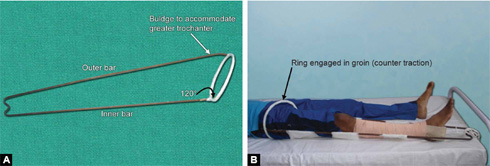

Thomas Splint (Figs. 1.28A and B)

It was designed by H O Thomas for tuberculosis of knee. It has one outer bar, one inner bar and one ring. Ring is at an angle of 120° to the inside bar and the outer bar has a curve to accommodate the greater trochanter.

Figs. 1.29A and B: (A) Cramer wire splint and (B) it can be easily bent to support fractures of limbs.

Size and preparation of Thomas splint: Appropriate length of the Thomas splint should be chosen for proper splintage. Ring size is chosen by adding 2 inches to the thigh circumference at the highest point of groin. Length is measured by adding 6 inches to the length from highest point on the medial side of groin to heel. After having chosen the appropriate size Thomas splint is prepared by padding of it by cotton bandages and cotton. Ring should also be padded well to avoid impingement on the skin.

Use: It is used for immobilization of lower limb in hip and thigh injuries. It is efficient and easy to use tool for transportation of patients with lower limb injuries. Fixed and sliding traction can also be given on Thomas splint.